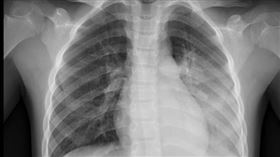

男星染寄生蟲肺變白!後才知2食物出問題

南韓演員權相佑2003年因電視劇《天國的階梯》紅遍全...